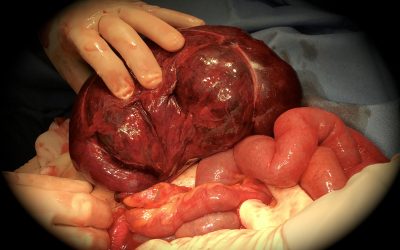

Neoformazione solida solitaria primitiva della milza: percorso diagnostico-terapeutico

di Enrico Ganz Nell’uso clinico, per “neoformazione solida primitiva della milza” si intende una malformazione o un tumore, benigno o maligno, che origina dal tessuto splenico, distinguendosi perciò dalle metastasi, che occasionalmente colonizzano la milza. Il...